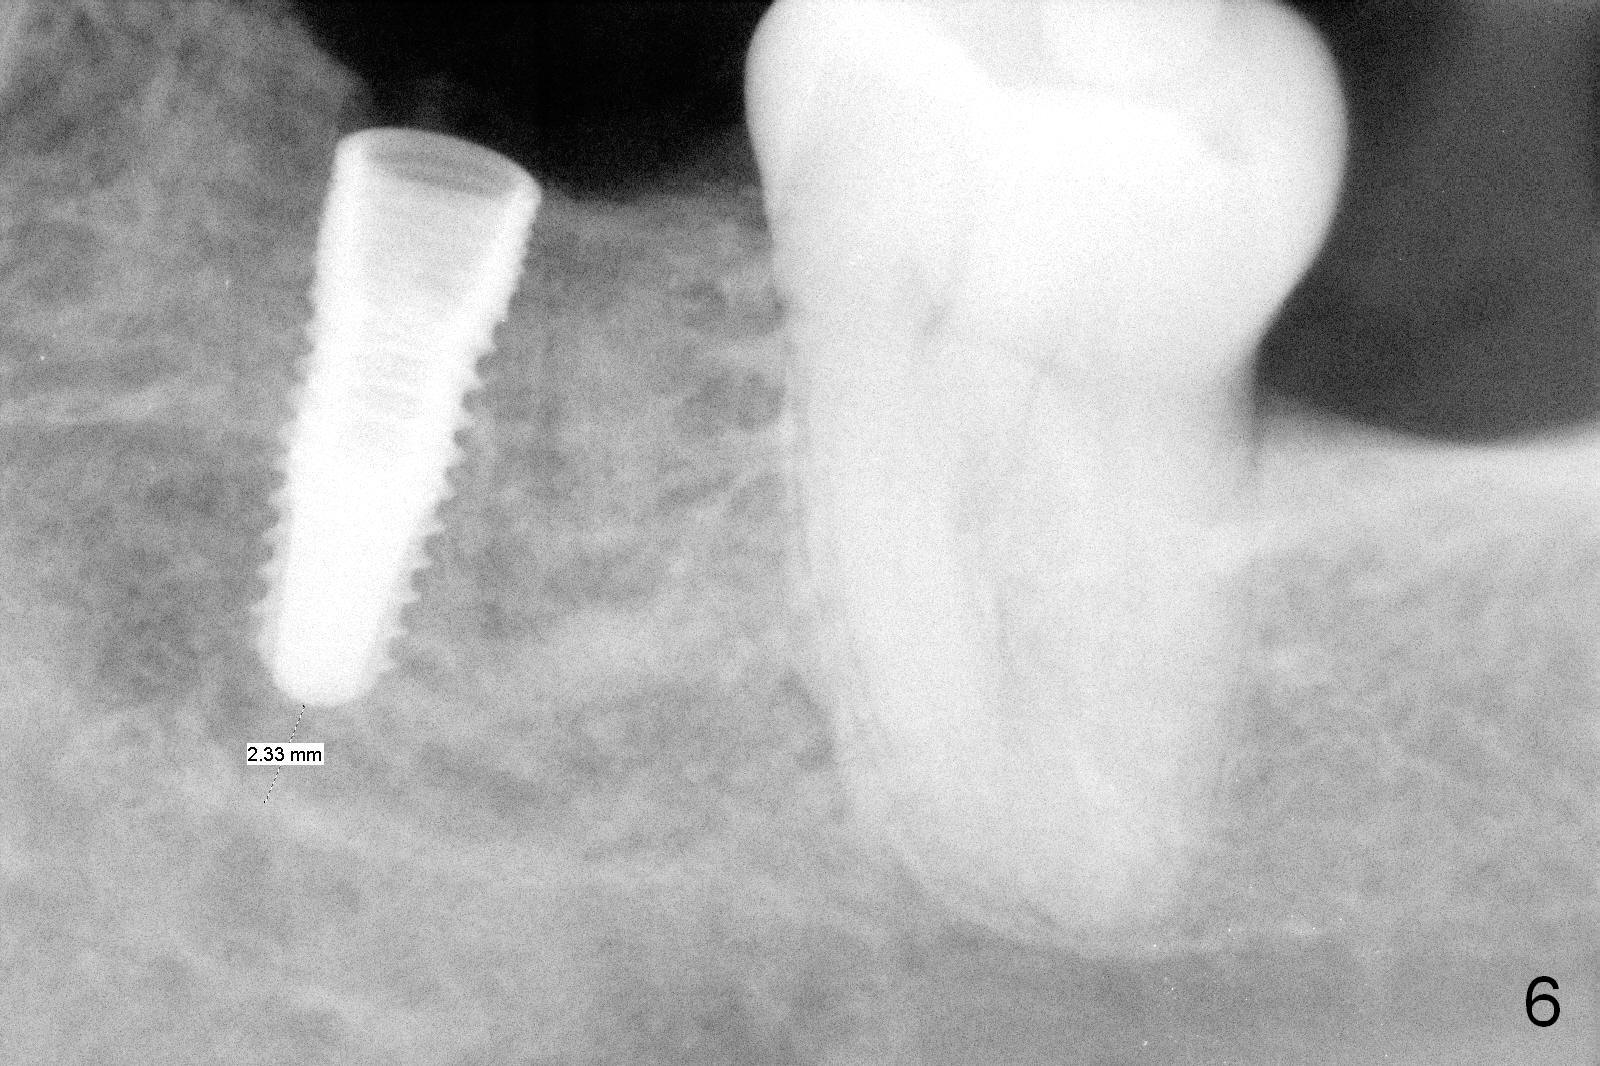

A 44-year-old black lady is a typical dental phobic. She has lost #19 for years with history of traumatic extraction. The ridge is atrophic (Fig.1). She is not comfortable with intraoral X-ray. So CBCT is taken. The coronal section shows that the bone density is low in the coronal ridge (Fig.2 arrowheads). It is difficult to determine the buccolingual width at crest; probably a 5.9x10 mm implant is appropriate (Fig.3). The most useful information from CT is height determination for the implant (Fig.4). The initial osteotomy depth is 10 mm (Fig.5); there is a large safety margin. There is a 2 mm clearance when a 4.5x12 mm implant is placed (Fig.6). Incision is sutured; a 8x4 (3) mm healing abutment is placed (Fig.7 arrowhead), followed by application of perio dressing. The latter remains stable 13 days postop thanks to the holding effect of the healing abutment (Fig.8 H). The wound has apparently healed when the dressing is removed (Fig.9). It appears that the edentulous space is extremely wide. The 4.5 mm implant may not sustain masticatory force. Limited orthodontic treatment appears to be necessary, using the implant as an anchorage to move the neighboring teeth (Fig.10 arrows). In fact the orthodontic treatment is not rendered. A crown is cemented 14 months postop. The cortical bone is thickened around the implant 15 months post cementation (Fig.11).